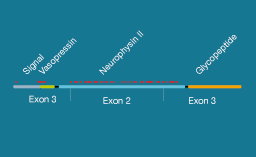

Diabètes insipides centraux génétiques

Spiess M, Beuret N, Rutishauser J. Genetic forms of neurohypophyseal diabetes insipidus. Best Pract Res Clin Endocrinol Metab. 2020 Jun 19:101432. Dans la majorité des cas, le diabète insipide central héréditaire est causé par des mutations du gène AVP. La transmission dominante est de loin la plus courante. Les symptômes […]